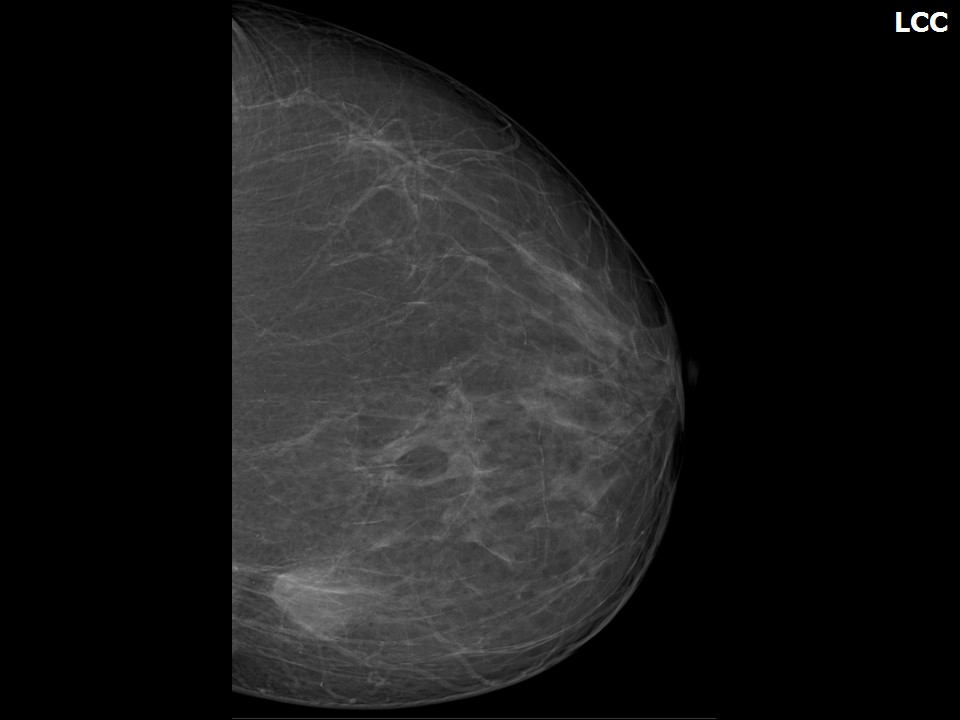

Что такое маммография: важность, процесс и результаты

Раздел: Необычные решения